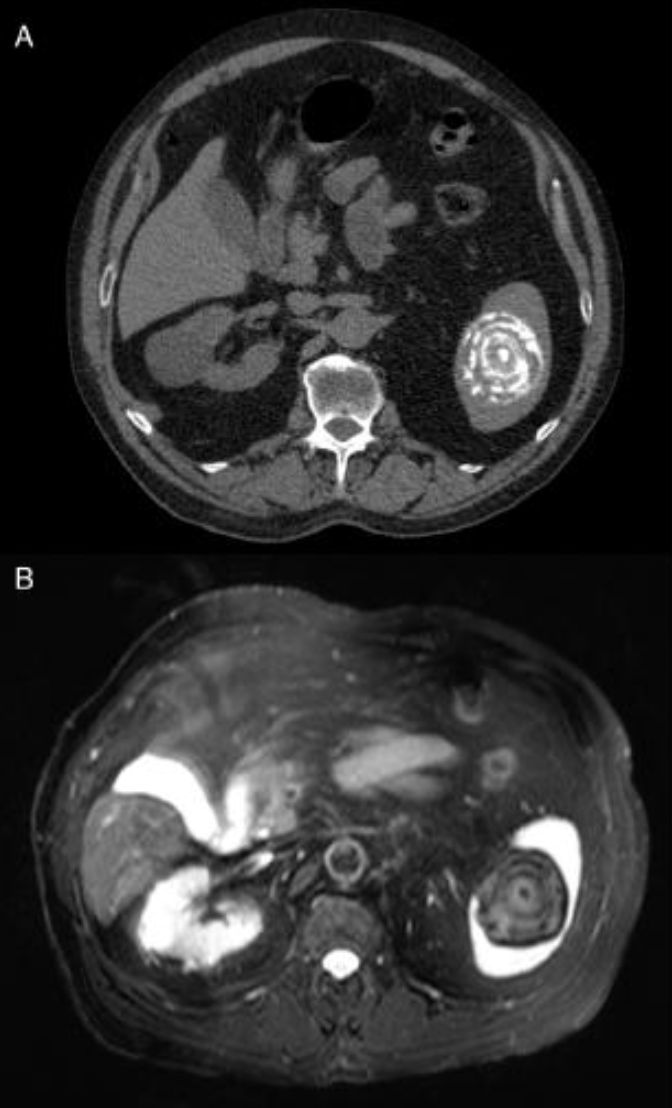

68yo female; Dx?

Dx: pancreatic serous cystadenoma.